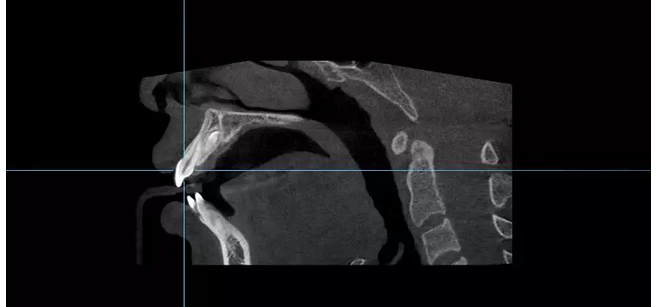

多生牙如何拔除?關(guān)鍵是定位 。手術(shù)前對(duì)埋伏多生牙進(jìn)行準(zhǔn)確定位能為手術(shù)進(jìn)路提供重要依據(jù)。

這個(gè)患者原本是到第一口腔光谷院區(qū)進(jìn)行牙齒矯正,正畸前拍片檢查意外發(fā)現(xiàn)存在埋伏多生牙。焦斌芳醫(yī)生通過CBCT三維重建影像,分析了解患者上頜前部埋伏多生牙的特性,包括多生牙的數(shù)目、形態(tài)、大小、埋伏位置、生長方向、牙根是否彎曲、對(duì)鄰近恒牙的影響等,精確定位多生牙埋伏于上頜骨內(nèi)的位置,明確與鄰牙的位置關(guān)系,確定手術(shù)方案及手術(shù)路徑,指導(dǎo)手術(shù)拔除埋伏多生牙。